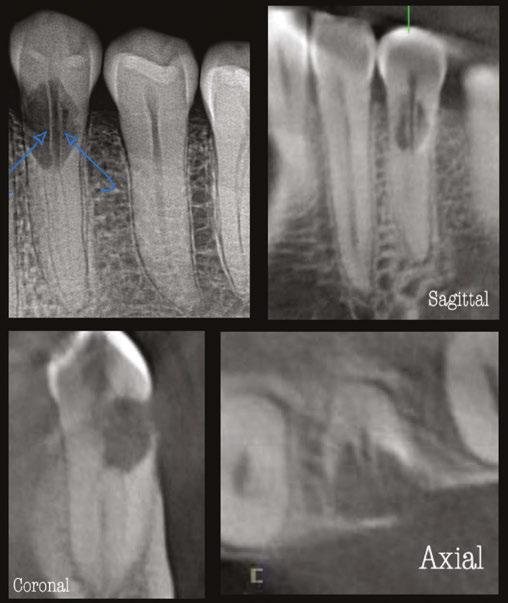

A 41-year-old male presented with a chief complaint of pain and swelling adjacent to tooth No. 10. The patient reported a history of trauma as a teenager, though he had not experienced issues until the recent onset of pain and swelling. Clinical examination revealed tenderness on the buccal gingiva around tooth No. 10, with sensitivity to percussion and biting. A small, fluctuant intraoral swelling was noted near the apex of tooth No. 10, and the tooth did not respond to vitality testing. Radiographic examination showed a large perforating internal resorptive defect near the apical third of the root (Figure 3A). CBCT (Veraviewepocs 3D R100; J. Morita) revealed significant alveolar bone loss adjacent to the defect, extending along the entire mesial side of

the apical half of the root of tooth No.10 and reaching the root of tooth No. 9 (Figures 3B and 3C).

A diagnosis of pulpal necrosis with acute apical abscess was made. All treatment options, including extraction with replacement by an implant or bridge, were discussed. The patient, motivated to retain the tooth, opted for root canal therapy and repair of the resorptive defect. Informed consent was obtained.

First visit

The patient was anesthetized with 1.7 mL of 4% articaine with 1:100,000 epinephrine (Septocaine®; Septodont®, Lancaster, Pennsylvania) via labial infiltration. Rubber dam isolation was achieved, and the tooth was accessed using a No. 2 surgical length carbide round bur. Necrotic pulp was encountered. Working length was established with a Root ZX® apex locator (Morita, Tokyo, Japan), and the canal was instrumented to a size 35 .04 Vortex Blue® rotary file (Dentsply Tulsa Dental, Johnson City, Tennessee). Care was taken to ensure that the files passed through the resorptive defect and entered the apical portion of the canal. The canal was irrigated with 5.25% sodium hypochlorite, and the EndoActivator® (Dentsply, Tulsa, Oklahoma) was used to sonically agitate the irrigant to promote thorough disinfection of the resorptive defect. The canal was dried with paper points, and calcium hydroxide (Ultracal™ XS, Ultradent Products Inc, South Jordan, Utah) was syringed into the canal and the defect. The tooth was then temporarily restored with Cavit® (3M ESPE, Neuss, Germany).

Second visit

Two weeks later, the patient returned for completion of the endodontic treatment, reporting that all symptoms had subsided. Clinical examination confirmed that the swelling had resolved. Calcium hydroxide was removed from the canal through instrumentation, irrigation, and activation with the EndoActivator. The canal was dried with paper points, and excess irrigant was removed using surgical suction with a micro-tip. A master gutta-percha cone was placed to the working length and confirmed with radiographic examination (Figure 3D). The canal was coated with EndoSequence® BC (bioceramic) sealer (Brasseler USA, Savannah, Georgia) to ensure sufficient sealer filled the resorptive defect. It was then obturated with gutta percha and BC sealer using the technique of warm vertical condensation (Figure 3E). The lingual access opening was restored with TPH Spectra® ST composite (Dentsply Sirona, Charlotte, North Carolina), and the patient was scheduled for recall to monitor healing.

At 1-year, 2-year, and 5-year recall visits, the patient was asymptomatic, and radiographs showed complete healing with full restoration of bone and lamina dura adjacent to the resorptive defect (Figures 3F and 3H). The patient expressed satisfaction with the outcome, having retained a tooth originally planned for extraction.

Figures 3A-3H: 3A. Preoperative periapical radiograph of tooth No.10 showing internal root resorption in apical third of root. There is significant alveolar bone loss adjacent to defect. 3B. Sagittal CBCT image of tooth No. 10 showing internal resorptive defect perforating on mesial aspect of root. Note adjacent alveolar bone loss extending proximally to tooth No. 9. 3C. Axial CBCT image of internal resorptive defect perforating on mesial aspect of root. There is thin layer of circumferential dentin remaining and extensive alveolar bone loss adjacent to the defect. 3D. Periapical radiograph showing gutta-percha cone fit. Gutta-percha cone passes through resorptive defect to contact apical portion of root canal. 2E. Immediate postoperative periapical radiograph of tooth No.10 once root canal was completed and resorptive defect was restored. 2F. Two-year follow-up showing complete healing of radiolucency adjacent to defect and reestablishment of PDL. 2G. Two-year follow-up CBCT. Coronal slice showing complete healing of radiolucency adjacent to defect and reestablishment of PDL. 2H. Five-year follow-up radiograph. Patient is completely asymptomatic